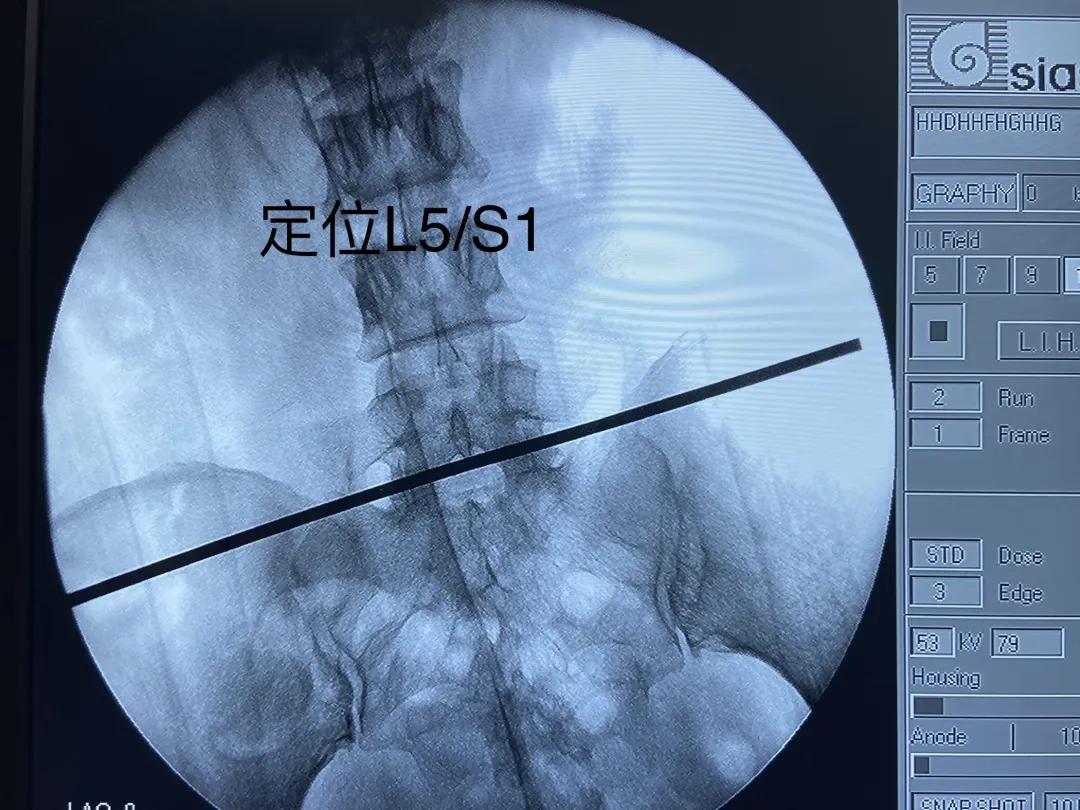

手术透视定位